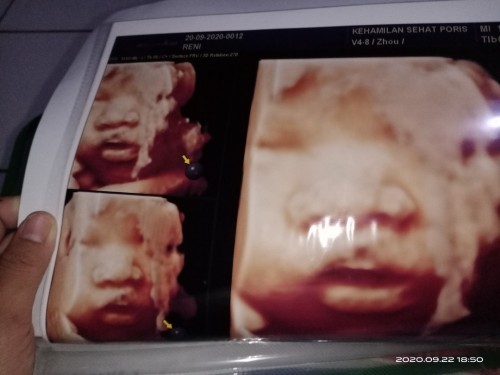

USG 4D

mau nanya Bun, pas USG lupa g nanya. Itu bibirnya knpa ya?

Klo kata dokter gak ada masalah ya percaya aja mom, itu kan hasil print usg didlm rahim kan gak bayi doang tp ada cairan ketuban dan plasenta jd hssil nya gak kya foto dicamera yg semuanya mulus

kemungkinan pasisi pas usg nya aja bun